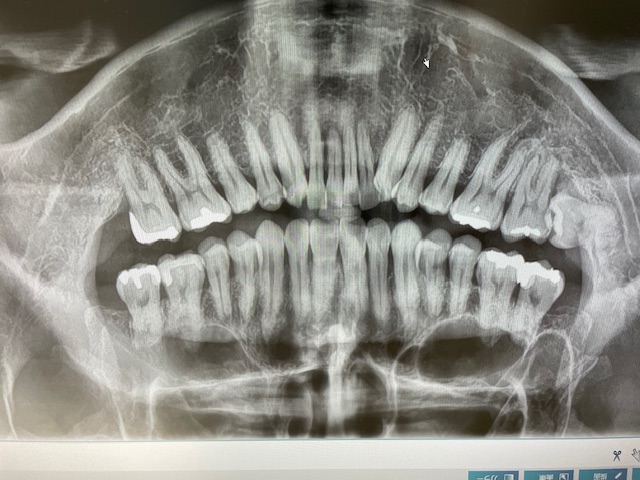

歯科用CT

CT

歯や顎の状態を3次元の立体画像で確認できます。

デジタルパノラマ

全体的に把握したいときに撮影します。